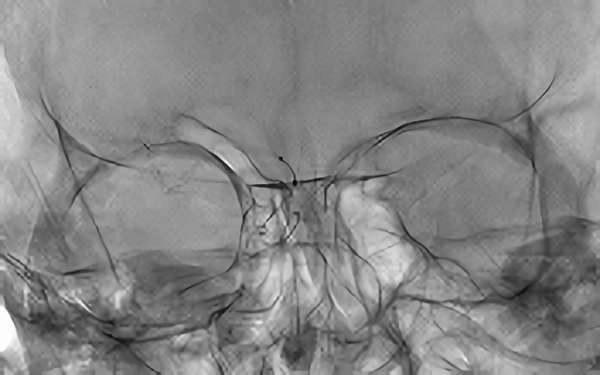

No.803 手術前